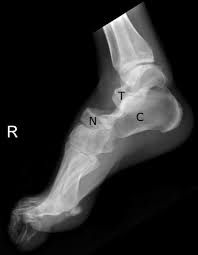

Subtalar Dislocations